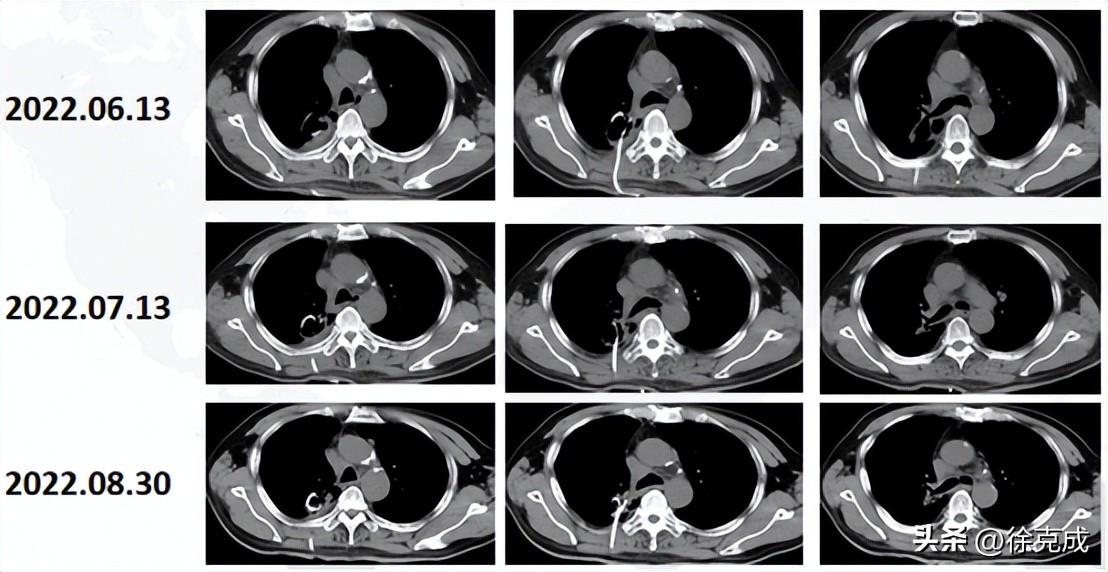

这位肺癌患者来院就诊的时候,肺上已经出现巨大空洞并伴随颅内转移,视力受到严重影响,生活质量极差,当地医院诊断其生存期只剩三个月。在复大接受四次介入治疗后,辅之以氢氧吸入,肿瘤标志物逐渐趋向正常,病变逐渐缩小。